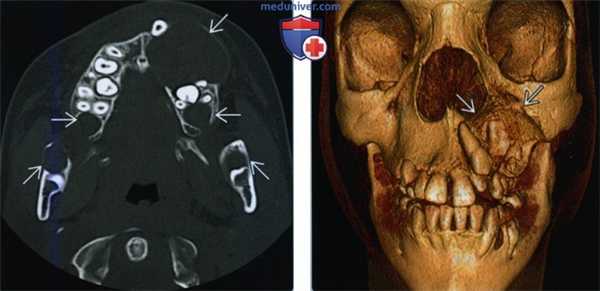

(Слева) При аксиальной КТ в костном окне у девятилетнего мальчика с синдромом базальноклеточного невуса визуализируются множественные двухсторонние литические очаги в верхней и нижней челюсти, типичные для кератокистозных одонтогенных опухолей.

(Справа) На 3D-реконарукции (вид спереди) у этого же ребенка лучше определяется объемное воздействие наибольшей опухоли на ближайшие зубы.г) Патология. Общая характеристика: